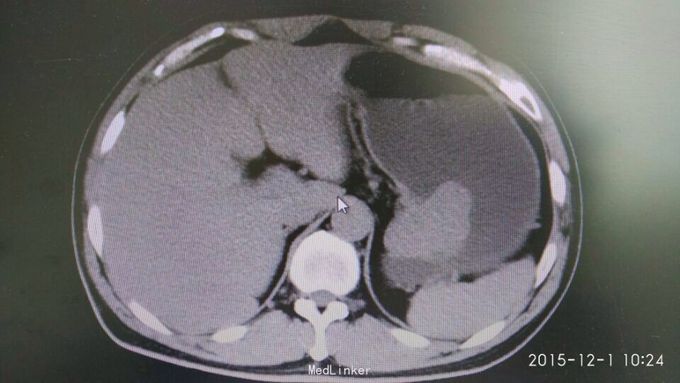

间断性上腹部隐痛,加重两月余。 于15年前左上腹间断隐痛,可忍,伴肩背部放射,活动后缓解,无恶心呕吐,大小便正常,未行特殊处理。2月前,上述症状出现并加重,伴腹泻,伴肩背部放射,无皮肤粘膜黄染。

巩膜无黄染,心肺无异常,腹部平坦,无腹壁静脉曲张,肠鸣音未见异常,左上腹压痛(-),无反跳痛,腹部未触及包块,肝脾肋下未及,Muephy(-),双肾区叩击痛(-),移动性浊音(-)

胃间质瘤 拟行胃间质瘤切除术

瘤体较大,超过5cm,术中注意与胰腺关系,如果压迫胰腺或压迫脾脏血管,是否考虑部分胰腺切除及脾切除,是否考虑胃空肠吻合。